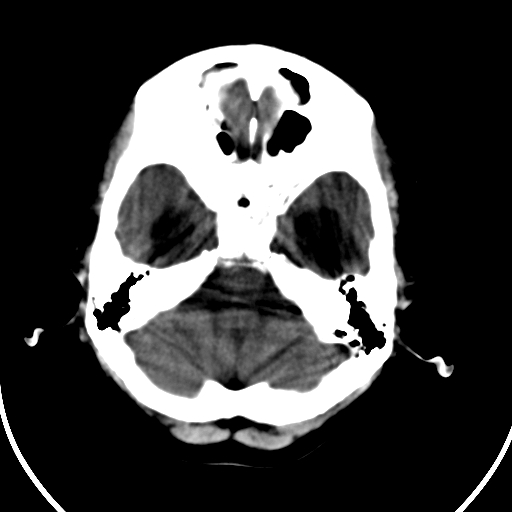

男,11岁

重度脑积水,但第四脑室扩大不明显,考虑导水管阻塞,建议mr。

右额叶单发近圆形低密度影,周边光滑,与侧脑室相通,考虑为孔洞脑并阻塞性脑积水。

右额叶内见一边界清楚,脑脊液密度的囊腔,无灰质内衬,并与脑室相通,四室以上脑室系统高度扩张。诊断:先天性脑穿通畸形伴梗阻性脑积水

需要与脑裂畸形鉴别:可见单侧或双侧衬有皮层的脑裂伸入额顶叶的白质内并与脑室相通